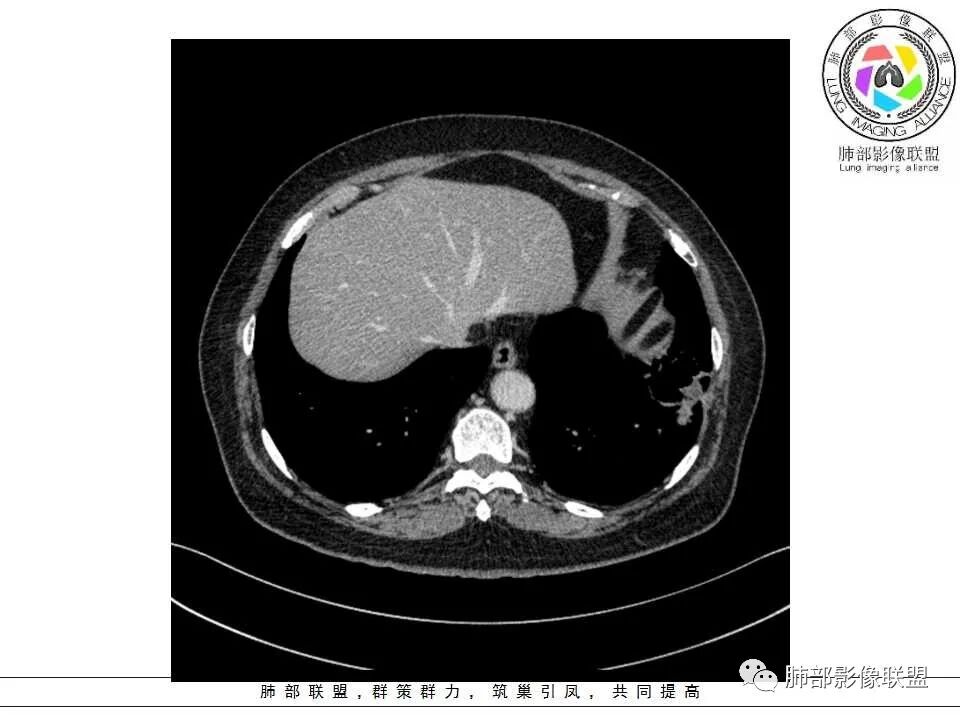

患者,女,65岁,2月余前受凉感冒后开始出现咳嗽,咳白痰,初发热2天,体温38℃左右,后降至正常,咳嗽无好转。近2日咳嗽加重,痰量增多,为黄白痰,无发热,无乏力、盗汗,无胸痛、胸闷,无头晕、头痛,无恶心、呕吐。PET-CT检查提示炎性病灶与恶性结节鉴别困难。

病灶分两部分

周围大片GGO

中央囊实性病变

囊腔有张力,外形有分叶,壁厚薄不均,有间隔,有强化